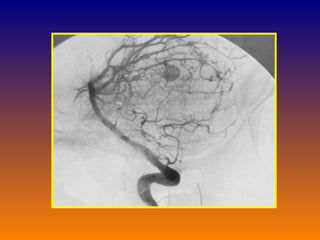

Subarachnoid hemorrhage Bed rest Analgesic Blood pressure control Oral nimodipine 60mg q6hx21 days Angiography for localization of bleeding If aneurysm  Immediate surgical clipping for Grade 1-3 patient without contraindication Grade 4-5 with intracerebral clot and deterioration

Subarachnoid hemorrhage Bedrest Analgesic Blood pressure control Oral nimodipine 60mg q6hx21 days Angiography for localization of bleeding If aneurysm Immediate surgical clipping for Grade 1-3 patient without contraindication Grade 4-5 with intracerebral clot and deterioration